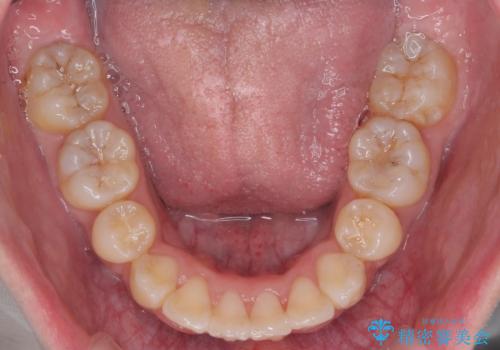

矯正後は口も閉じやすくなり、大変喜んでいただけました。

2-3年かかりますが、その後の70年の方が、長いのではないかと思います。

あきらめずにぜひ相談してください。